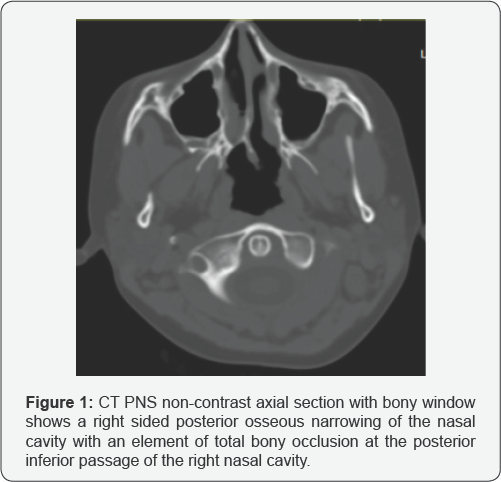

Imaging: CT scan of paranasal sinus was requested (Figures 1 & 2).

Findings of Non-contrast CT scan of PNS

a) Unilateral posterior osseous narrowing at the right posterior nasal cavity with an element of total bony occlusion at the posterior inferior passage of the right nasal cavity

b) Frothy air-fluid level noted opacifying the right nasal cavity.

c) No vomer bone thickening is noted

Diagnosis: Unilateral right sided choanal atresia